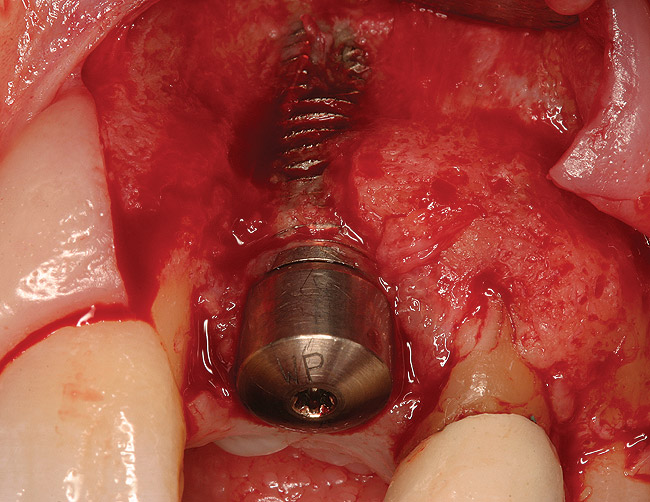

Figure 18  (Case 2) New implant in place 6 months after graft.

Figure 18

Figure 19  (Case 2) Allograft soft tissue placed at time of implant installation.

Figure 19